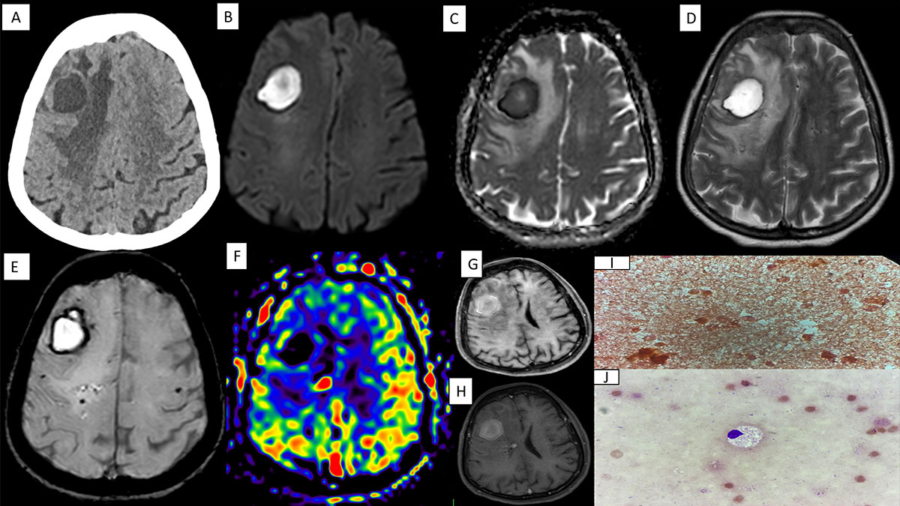

59-Year-old lady, a known case of chronic liver disease with portal hypertension presented with progressive left hemiparesis over three months.